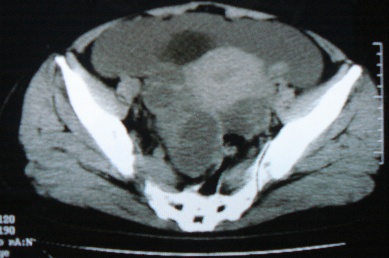

ct10755,女,48岁。感腹胀一周入院。

考虑右侧卵巢囊腺癌并腹腔转移、子宫肌瘤

支持右侧卵巢囊腺癌并腹腔转移

考虑右侧卵巢囊腺癌并腹腔转移可能性大、子宫肌瘤

支持:右侧卵巢囊腺癌并腹腔转移,或囊腺瘤破裂腹腔种植。

支持:右侧卵巢囊腺癌并腹腔转移、腹水、盆腔积液。

考虑为右侧卵巢囊腺癌并腹腔转移、腹水、盆腔积液.

右侧卵巢囊腺癌并腹腔转移,腹水。

支持右侧卵巢囊腺癌并腹腔转移(大量腹水)。